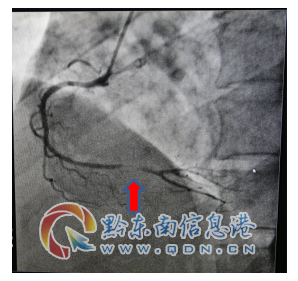

該患者入院查肌鈣蛋白、心肌酶增高,復查心電圖提示“Q波加深、ST段下移較前明顯”,結合輔助檢查結果陳文海主任對患者病情診斷為急性心肌梗死,考慮患者合并有糖尿病、甲亢等多種病癥,病情緊急,需按照胸痛中心急性心肌梗死流程緊急處理。經過該院心血管內科專家的會診評估,認為及早行冠脈介入診療對患者是有益的。征得該患者及家屬的同意后,立即啟動導管室行冠脈造影檢查,造影提示右冠脈遠段重度狹窄病變,在李健民副主任醫師的指導下,心血管內科陳文海主任、楊文林醫師對患者繼續行藥物球囊擴張術,選擇支架植入為補救治療方案。冠脈介入過程謹慎細致,最后判斷冠脈藥物球囊擴張術對患者獲益更大后,予以藥物球囊擴張術,不需植入冠脈支架,造影復查嚴重狹窄病變處經藥物球囊擴張術處理后,殘余狹窄小于30%,達到治療效果。手術過程歷經不足半小時,成功開通狹窄病變的冠脈血管,TIMI血流3級,手術效果滿意,術后患者安返病房,未再出現胸痛癥狀。

術前病變(箭頭所示)